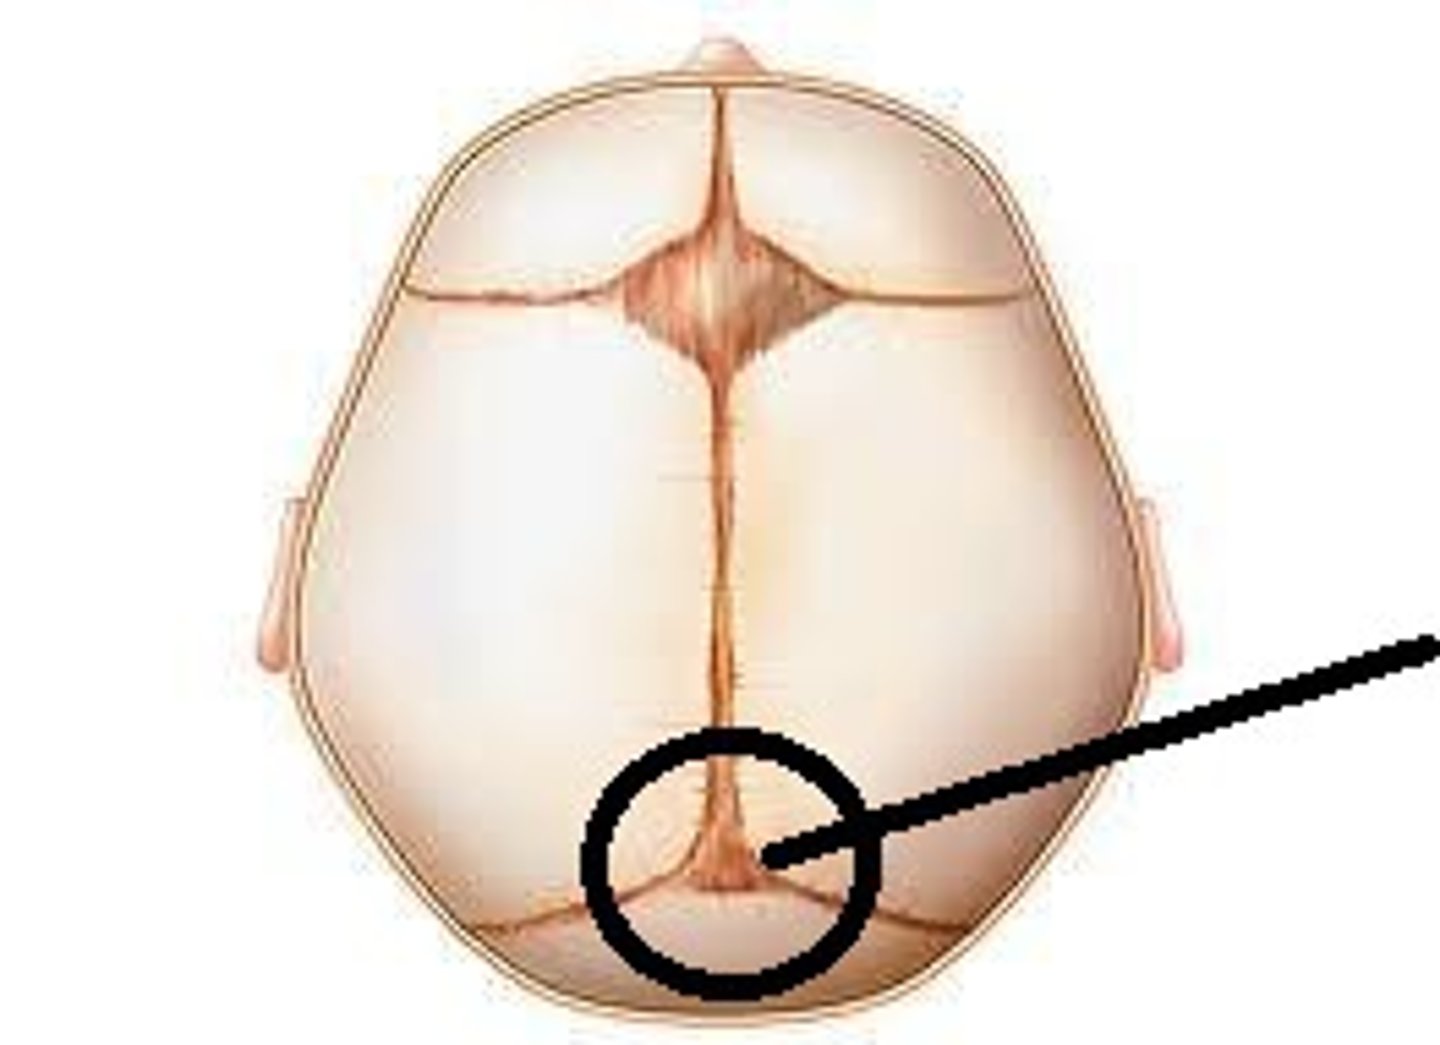

lambda

posterior fontanel